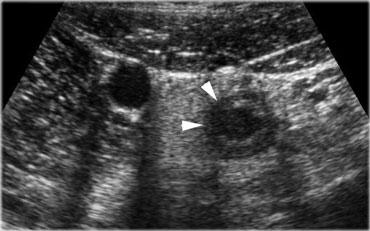

Viêm hồi manh tràng nhiễm khuẩn ở bệnh nhân có triệu chứng lâm sàng của viêm ruột thừa. Có hình ảnh dày thành lớp niêm mạc và dưới niêm mạc rõ rệt của hồi tràng và manh tràng.

Hình bên trái là một phụ nữ 26 tuổi với các triệu chứng lâm sàng của viêm ruột thừa.

Siêu âm cho thấy van hồi manh tràng nổi bật và dày thành lớp niêm mạc và dưới niêm mạc rõ rệt của hồi tràng và manh tràng.

Các hạch bạch huyết phì đại được phát hiện tại gốc mạc treo ruột.

Ruột thừa bình thường.

Phẫu thuật cắt ruột thừa đã được hủy bỏ.

Ngày hôm sau bệnh nhân xuất hiện tiêu chảy và kết quả cấy phân cuối cùng phát hiện Campylobacter jejuni.

Viêm hồi manh tràng nhiễm khuẩn. Siêu âm cho thấy dày thành lớp niêm mạc và dưới niêm mạc. Đại tràng lên co thắt với hình ảnh bờ múi nổi bật. Ruột thừa bình thường (mũi tên).

Trong viêm hồi manh tràng nhiễm khuẩn, siêu âm cho thấy các đặc điểm khá đặc trưng.

Có hình ảnh dày lan tỏa lớp niêm mạc và dưới niêm mạc của hồi tràng tận và manh tràng.

Ruột thừa phải bình thường trên siêu âm (Hình).